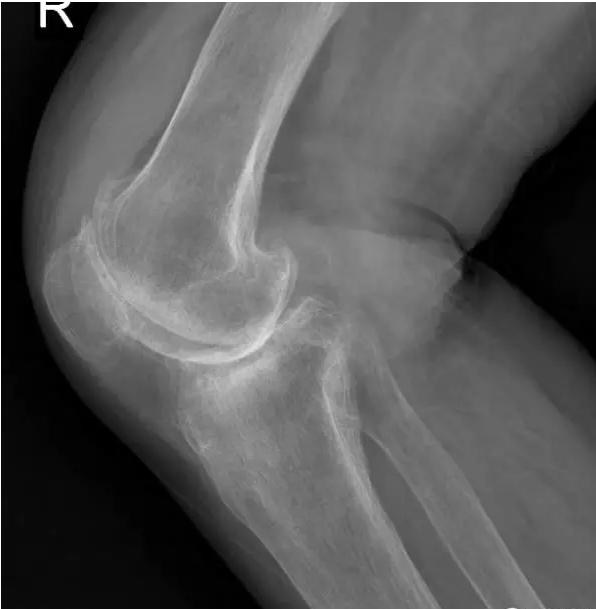

术前片:

晚期:骨关节炎表现为膝关节明显疼痛,休息后常无缓解,伴有活动受限,可并发畸形,X 线片可见关节周围有明显的骨赘形成,或可见游离体,关节间隙明显狭窄,甚至消失。

对于晚期(重度)骨关节炎,保守治疗无效时,要积极考虑手术治疗。目前效果最佳的手术方式即为关节置换手术,其他手术方式如关节融合手术等效果较关节置换术相差较大,已不在临床广泛使用。关节置换手术的目的是缓解患者疼痛,矫正关节畸形,恢复关节功能,恢复正常生活。对于老年人来说,积极的手术治疗可以有效恢复其日常生活,避免因疼痛及活动障碍导致患者扶拐或坐轮椅,有效减少因缺乏运动导致的心肺功能障碍及精神问题发生。经过几十年的发展,目前关节置换技术已十分成熟,临床上目前采用的微创技术,手术创伤小,术中出血非常少,术后第二天患者即可下地行走,三月之后即可恢复正常生活及功能。至于人工假体使用寿命,目前进口关节多为20-30年,能满足60-70岁患者的需求。需要注意的是,在行关节置换手术之后,患者仍需要进行积极的康复治疗,包括关节活动度及周围肌力的锻炼等,这样才能达到最佳的手术效果。